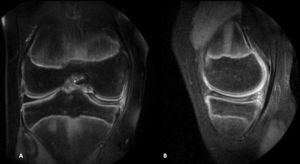

Clinical caseA male, 14-year-old patient presented for consultation due to pain in both knees of insidious onset and predominantly in the right knee, intermittently of 5-year duration. He played basketball and tennis but was frequently in discomfort during the sports activities and had resorted to the use of non steroid anti-inflammatories to be able to practice these sports. On examination pain presented in the medial joint line, with a positive McMurray sign, a negative Lachman sign, without any tears or swelling, with flexion of 140° and extension of 0°, and the remainder of the examination resulting normal. A magnetic resonance of the right knee (Fig. 1) was requested where the integrity of the cruciate and collateral ligaments was observed, the external meniscus of normal morphology and appearance, with no rupture lines. The medial meniscus was discoid with intrameniscal deterioration, with no clear rupture opening to the joint surfaces. According to the Watanabe9 classification (which divides the discoid menisci into complete, incomplete and Wisberg-ligament variant) this was a complete discoid meniscus. The joint cartilage of the kneecap showed no remarkable anomalies. Magnetic resonance was carried out on the left knee where an medial discoid meniscus of similar characteristics to that of the right knee was observed, with no other findings. In both knees the same medial discoid meniscus presented with intrasubstance deterioration, was complete, and the morphology was block-shaped not tapered. A block-shaped morphology of the discoid meniscus makes it more vulnerable to deterioration and rupture, according to Ayala et al.16